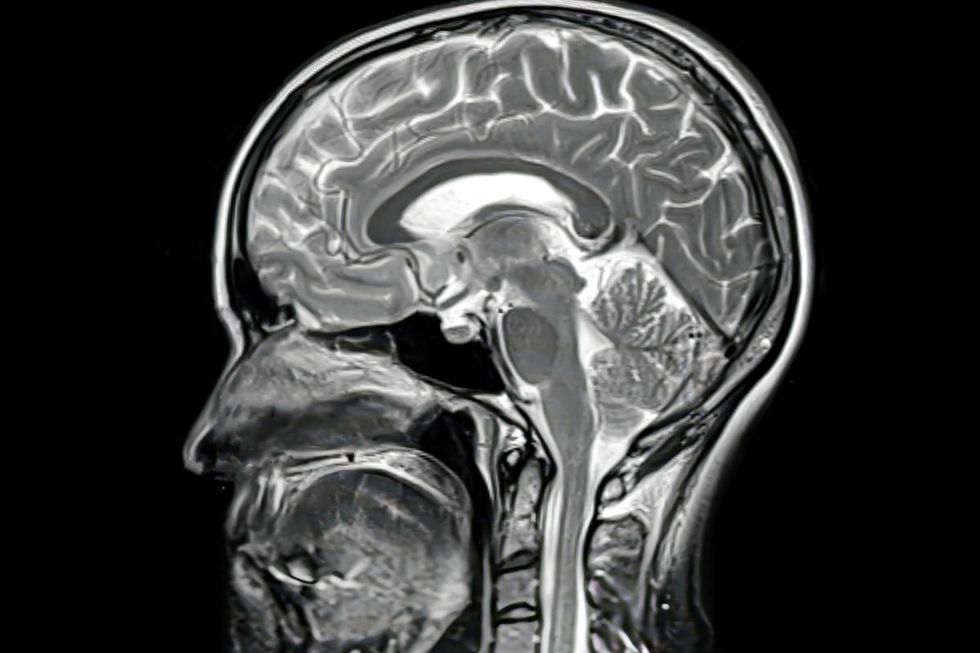

Your food choices don't just shape your waistline; they could also alter the shape of your mind.

According to a major study published in JAMA Neurology, people who closely followed the DASH-style diet had a 41 per cent lower chance of experiencing cognitive decline.

The DASH diet – which stands for Dietary Approaches to Stop Hypertension – showed the strongest protective effects on brain function compared to five other healthy eating patterns, with leafy greens, fruits, fish and tea all linked to better cognitive outcomes.